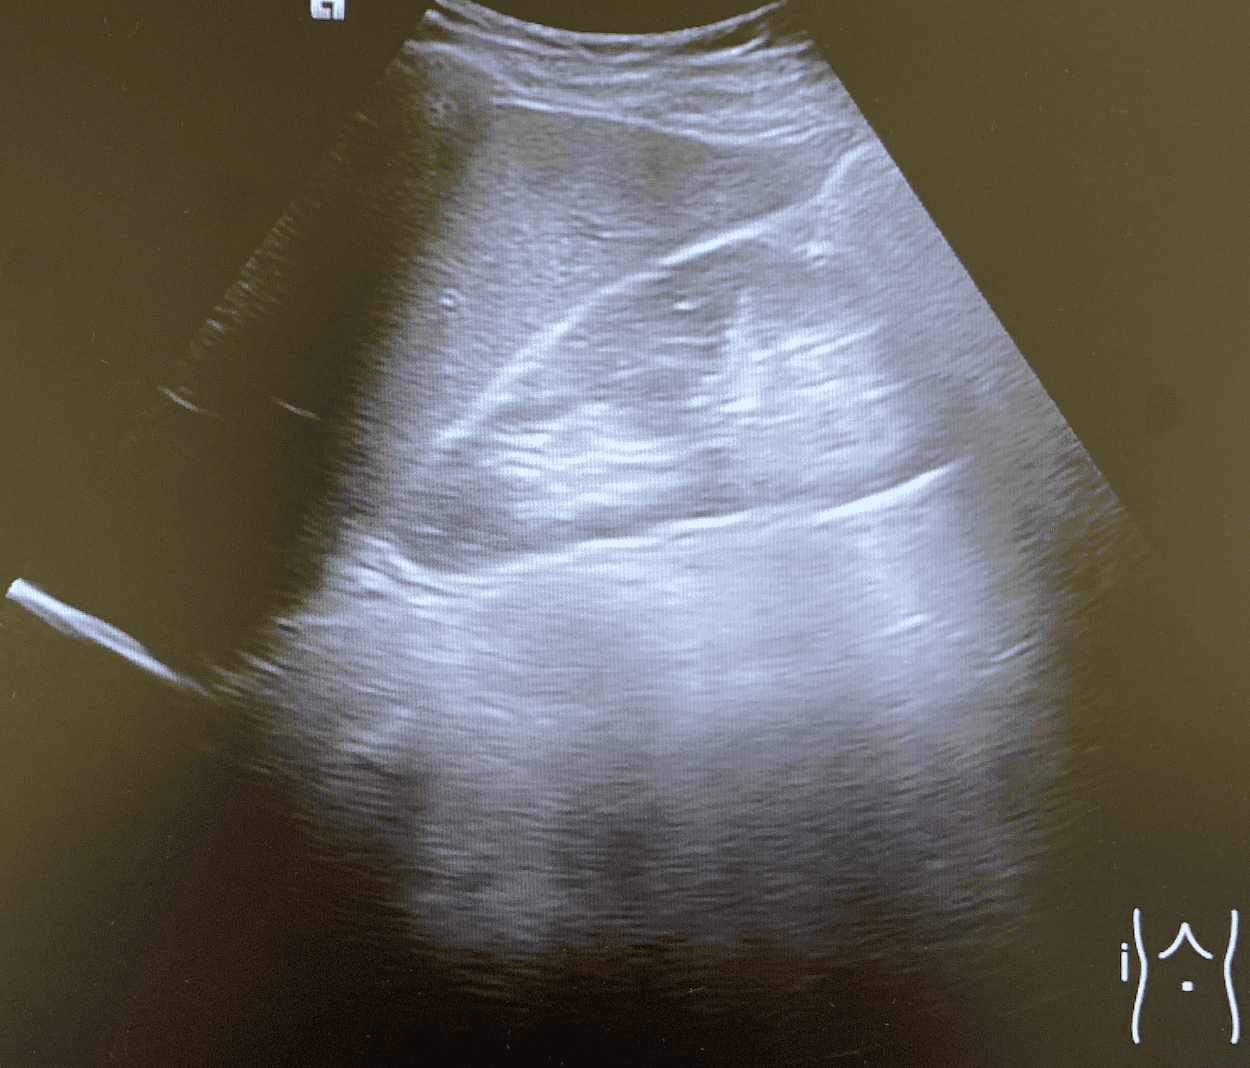

Se realizan cortes longitudinales y transversales de ambos riñores y de vejiga.

Riñones de ecoestructura, tamaño y localización normales. Relación córtico-medular normal. Sin signos de hidronefrosis.

Vejiga repleccionada de paredes lisas, sin evidencia de crecimiento en su interior. Visualización de ambos jets ureterales. Se observa fenómeno de centelleo en trayecto ureteral derecho, sugestivo de litiasis.